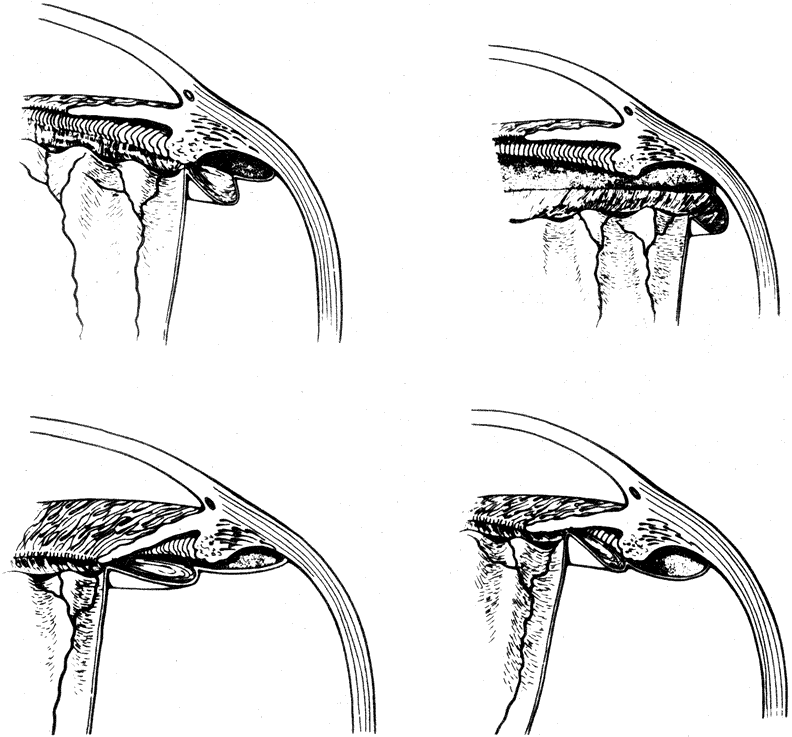

The pathogenesis of macular holes has been controversial for some time. Initial reports suggested an association with hormonal changes, disorders of the retinal pigment epithelium, and retinal thinning, as well as systemic vascular diseases and cystic retinal degeneration.84 However, as the ability to examine the vitreous has improved, the central role of the vitreous in the pathogenesis of macular holes has become increasingly clear. Early observations suggested that shrinkage of the vitreous fibers that extend through the vitreous base may account for macular hole formation.85 Subsequent studies have suggested that the shrinkage of the prefoveal vitreous cortex is the central and initiating event in the formation of macular holes. Gass' initial classification of macular holes proposed in 1988 was the first classification attempting to explain the clinical presentation and pathophysiology in the development of full-thickness macular holes. This classification was reappraised and updated in 1995 and stratifies the formation of macular holes into four separate stages86 (Fig. 11). Although these four stages remain useful for the clinical description of macular hole formation, more recent imaging techniques using the scanning laser ophthalmoscope, the retinal thickness analyzer, and OCT have caused many investigators to reconsider the pathogenesis of macular holes.

Fig. 11. Updated diagram of proposed development of idiopathic macular holes according to Gass. (Gass JDM: Reappraisal of biomicroscopic classification of stages of development of a macular hole. Am J Ophthalmol 1995;119:752)